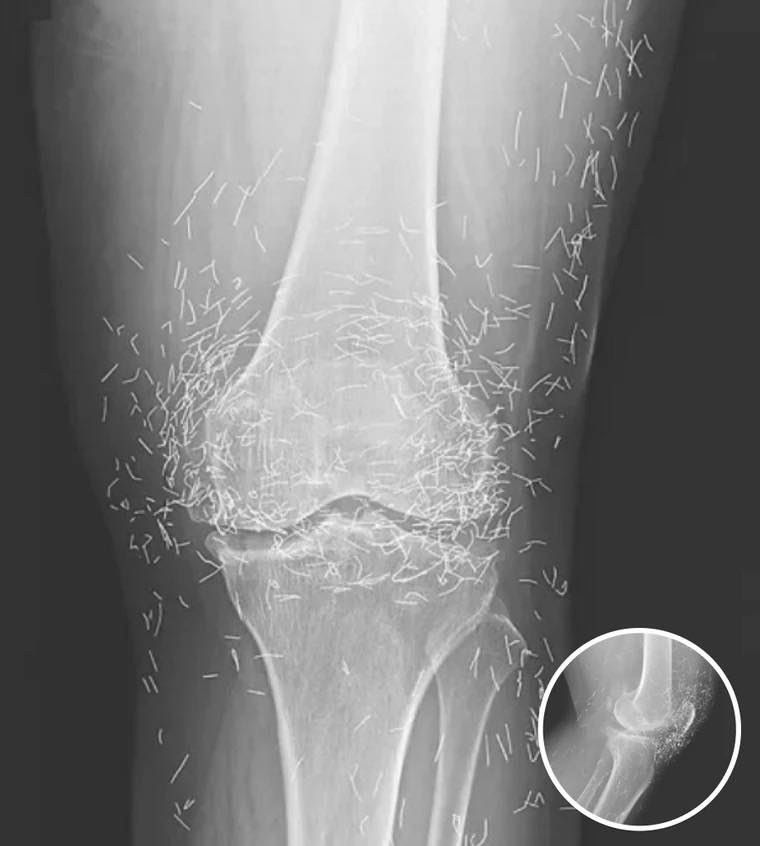

Doctors Stunned After Looking At This X-Ray Of Woman Suffering Joint Pain

A 65-year-old woman in South Korea experienced a shocking medical discovery when doctors found hundreds of tiny gold needles embedded in her knee tissue during a routine X-ray. She had been suffering from chronic osteoarthritis, a condition that causes joint pain, stiffness, and inflammation due to cartilage breakdown.

After conventional treatments such as painkillers and anti-inflammatory drugs failed to relieve her symptoms — and caused unpleasant side effects — she turned to acupuncture, a traditional therapy commonly practiced in many parts of Asia. Acupuncture involves inserting thin needles into the skin to stimulate specific points for pain relief or other health benefits.

In this case, the needles were intentionally left in her body as part of a long-term treatment strategy. Some practitioners believe that leaving gold needles or threads in place can provide ongoing stimulation to the affected area. However, medical professionals warn that this approach carries significant risks.